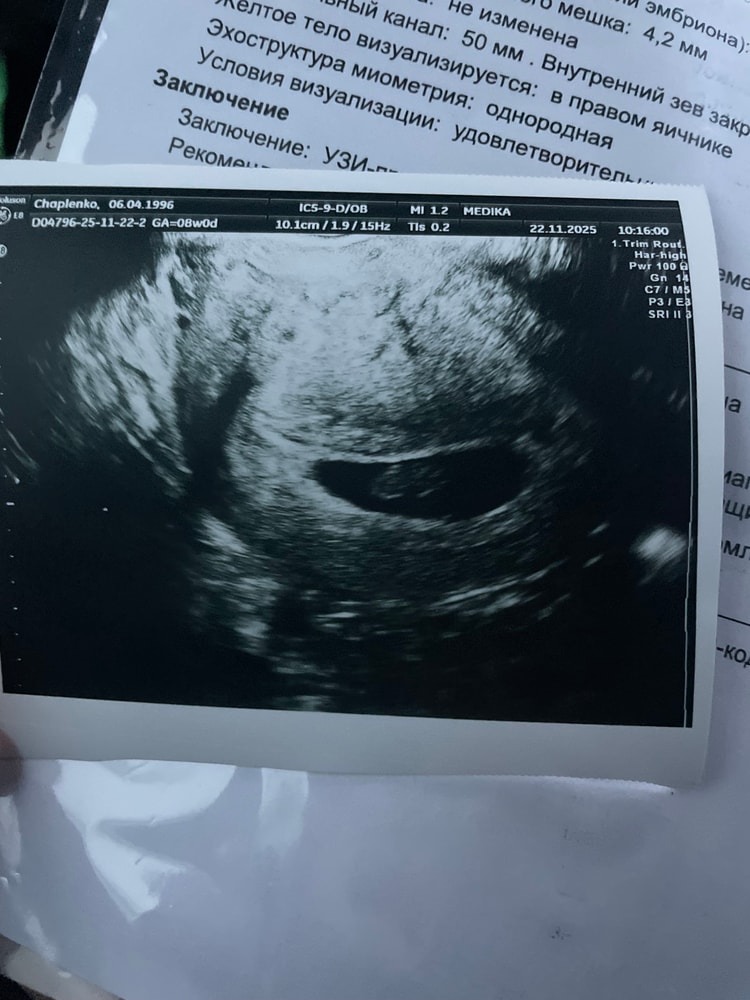

УЗИ 8 недель

УЗИ 22 ноября ктр -20мм (теперь малышок по сроку )🙏

22.11.2025